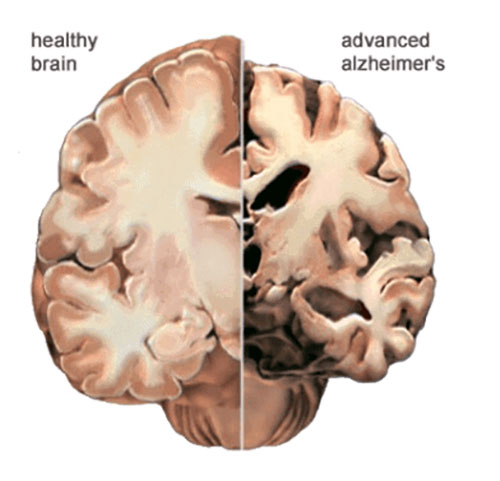

هیچ دلیلی برای زوال عقل وجود ندارد. همان طور که گفته شد، انواع زوال عقل از آسیب سلول های مغزی ناشی می شود. علاوه بر این، هر نوع زوال عقل ممکن است با آسیب های مختلف و مناطق مختلف مغز همراه باشد. به طور کلی، آسیب به سلول های مغزی در توانایی آنها برای برقراری ارتباط با یکدیگر اختلال ایجاد می کند، که منجر به مشکلات رفتار و تفکر می شود.

آلزایمر حدود 60٪ تا 80٪ موارد زوال عقل را شامل می شود و یک بیماری پیشرونده مغزی است که بر حافظه، روند فکر، رفتار و توانایی به خاطر سپردن اطلاعات تازه آموخته شده تأثیر می گذارد.